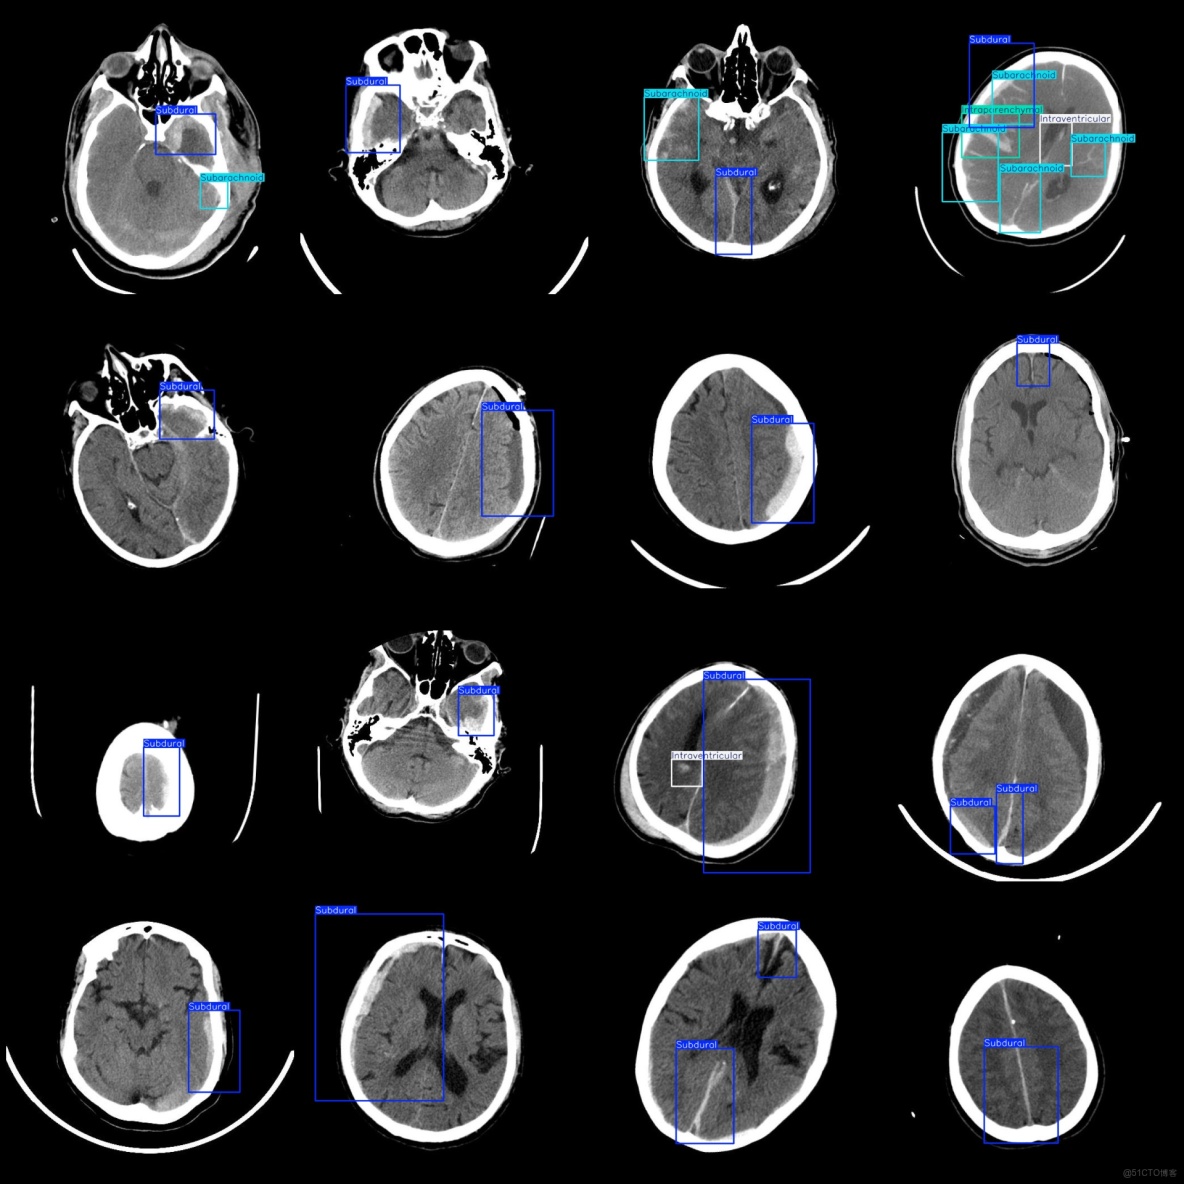

圖片預覽:

標註例子:

標註類別名稱(注意yolo格式類別順序不和這個對應,而以labels文件夾classes.txt為準):["Intraparenchymal","Intraventricular","Subarachnoid","Subdural"]

Intraparenchymal (腦實質內出血) 框數 = 655

Intraventricular (腦室內出血) 框數 = 141

Subarachnoid (蛛網膜下腔出血) 框數 = 579

Subdural (硬膜下出血) 框數 = 4156